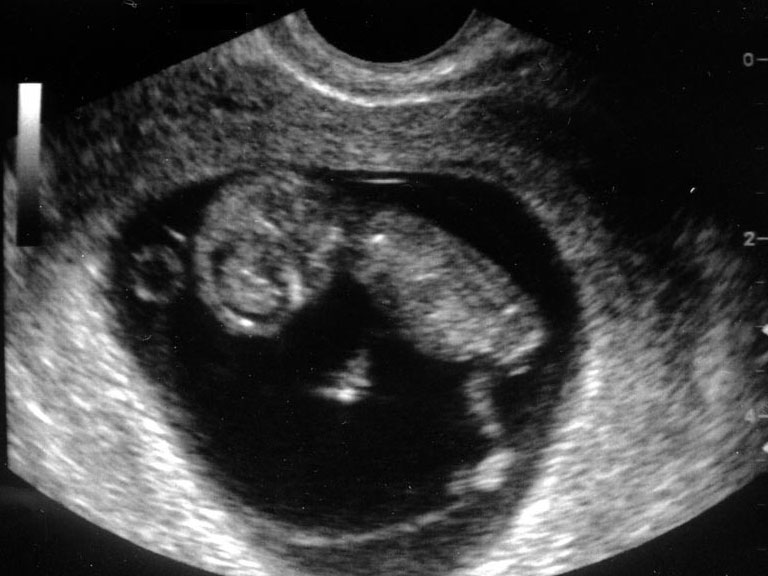

1분기 (착상부터 임신 14주까지)

1. 임신낭 위치

2. 배아 존재 확인

3. 배아의 정둔장 체크 (즉 배아의 머리끝부터 엉덩이 끝까지 길이)

4. 배아나 태아의 생존 여부 즉 심박동 유무와 횟수 확인

5. 배아나 태아의 수 확인

6. 자궁과 그 부속기인 난소등 검사